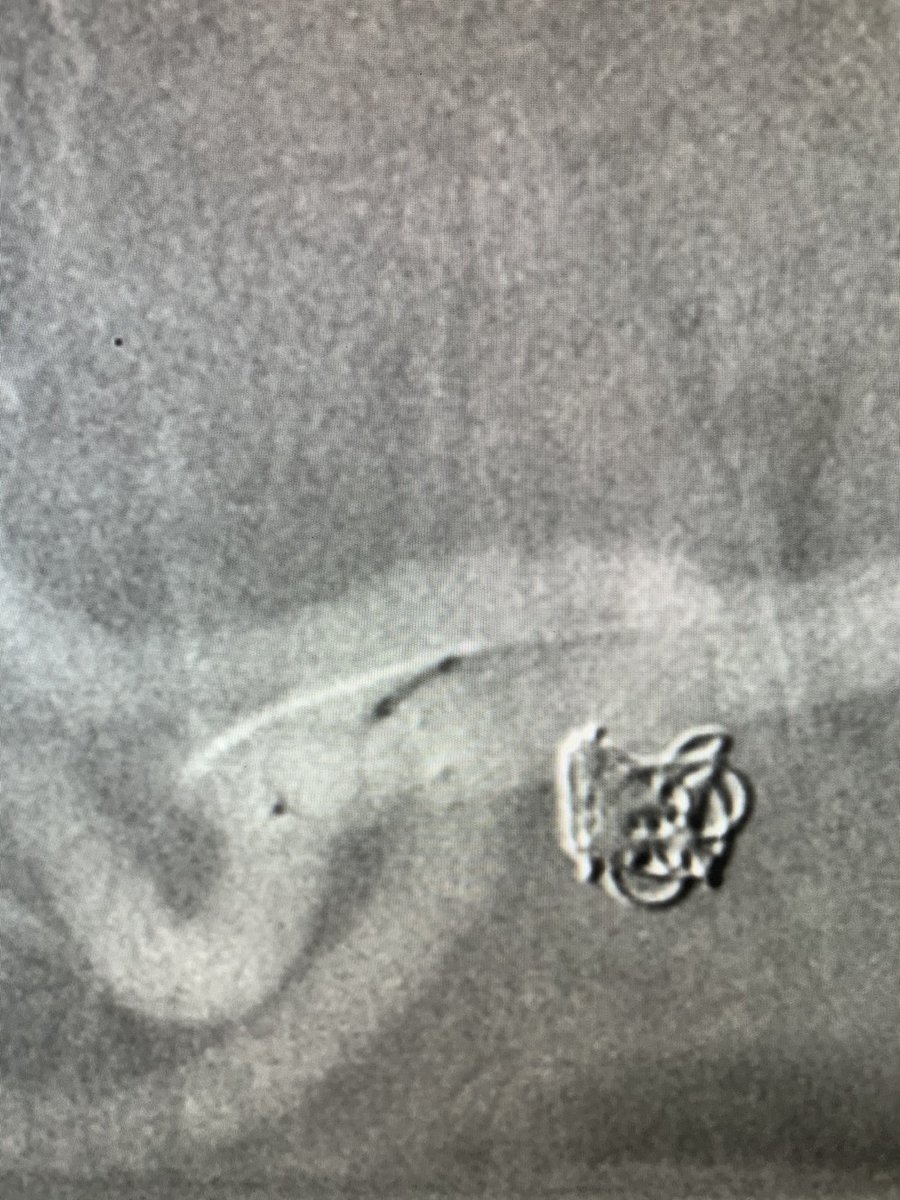

WEB can be used in various anatomical locations. We treated a wide-necked renal artery aneurysm with a WEB by ”corking” the neck. Immediate contrast stagnation!